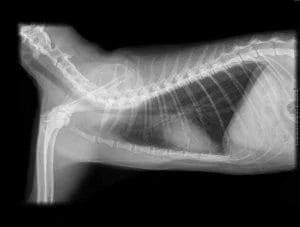

En veterinarias Murillo contamos con estudios rayos X para poder analizar de manera correcta a tus mascotas.